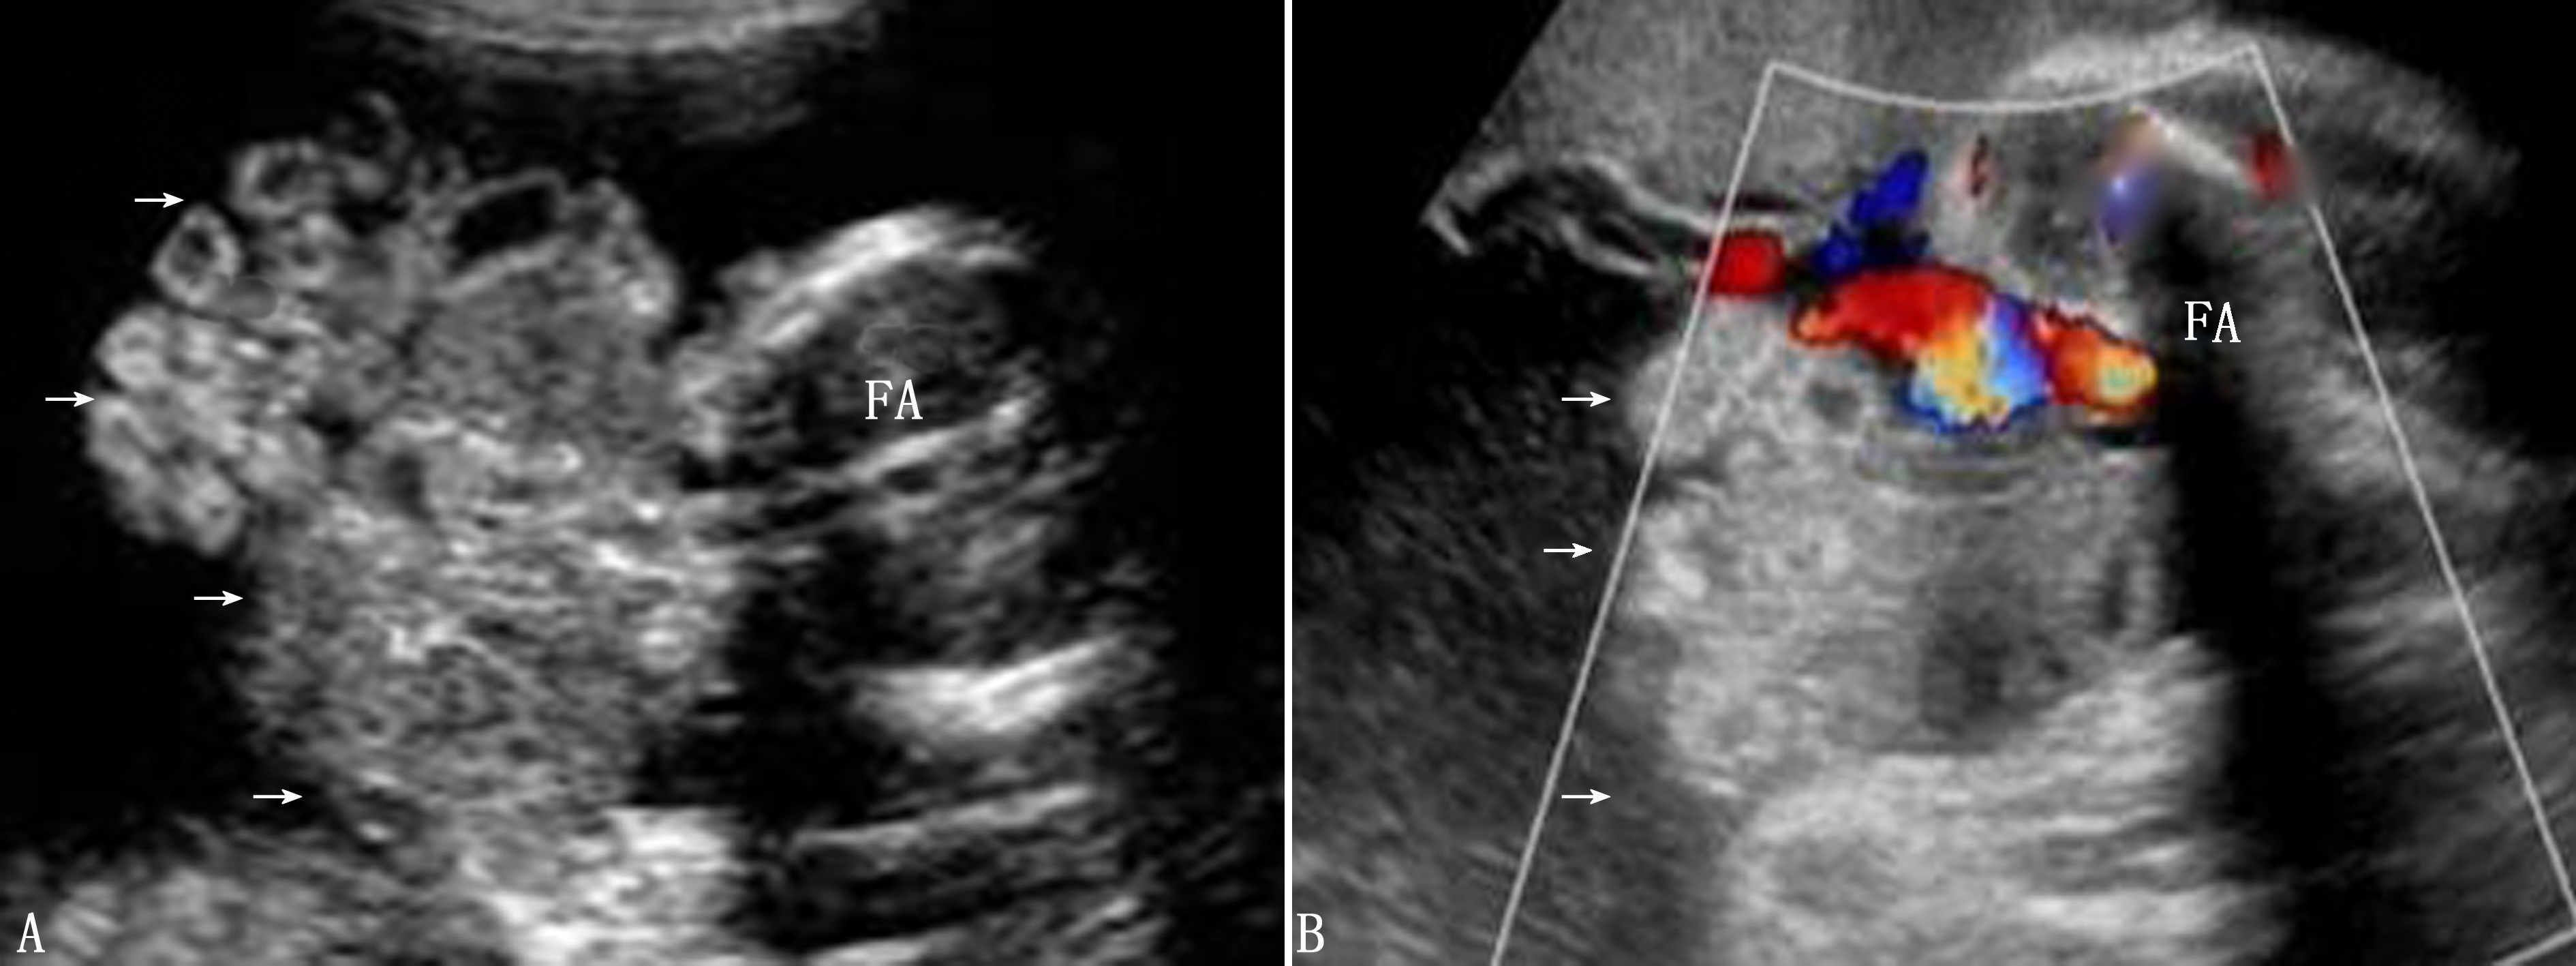

超声诊断:腹裂常发生于脐带的右侧,极少发生于左侧。声像图上可见腹壁皮肤强回声线连续性中断,一般为2~3cm,腹腔内脏器外翻至羊膜腔内,表面无膜覆盖,腹围小于相应孕周大小,常常伴有羊水过多(图2)。外翻的肠管有时可见局部节段性扩张,管壁增厚,当扩张的肠管突然消失时,提示有发生肠穿孔的可能。

图2 孕16周胎儿腹裂(→)声像图,脐带血流位于包块一侧